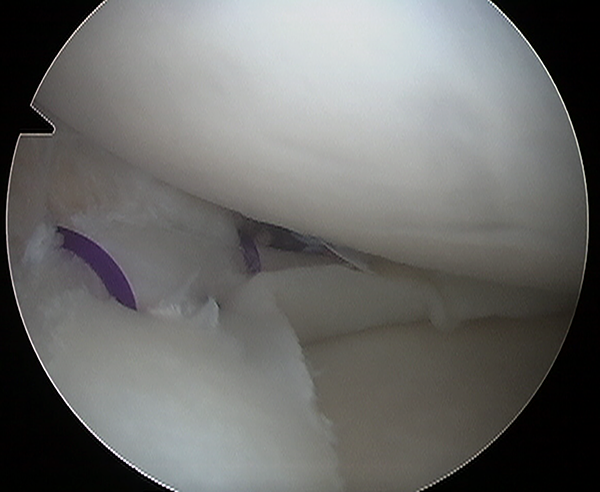

Figura 1:

Paciente de 20 años, rodilla izquierda. Vision artroscopica por portal anterolateral de una ruptura del menisco interno. Debridamiento con shaver de la lesion.